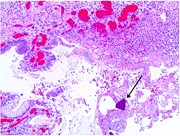

Perforated jejunal diverticulum: a rare case of acute abdomen

Rishabh Sehgal and others

Journal of Surgical Case Reports, Volume 2016, Issue 10, October 2016, rjw169, https://doi.org/10.1093/jscr/rjw169